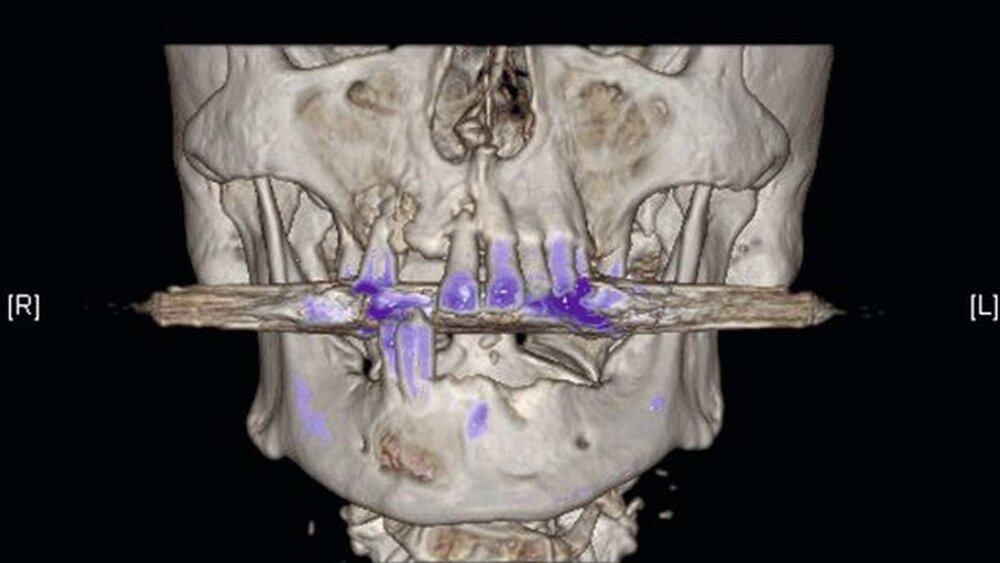

Die Computertomografie der Nasennebenhöhlen (NNH-CT) (nativ) zeigte dann das Ausmaß der knöchernen Destruktion. Neben der ausgedehnten generalisierten Nekrose des Oberkiefers konnte nebenbefundlich eine zystische Läsion im Bereich des Unterkiefers Regio 41 bis 45 diagnostiziert werden. Voraussichtlich ging diese vom Wurzelrest des Zahnes 41 aus. Weiterhin bestand eine totale Verschattung beider Sinus maxillaris und eine akzentuierte Lymphadenopathie in allen abgebildeten Leveln.